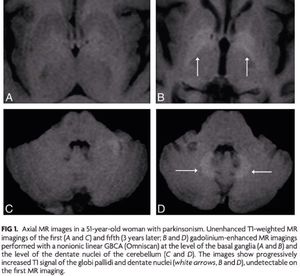

Recent literature confirms that gadolinium deposition occurs in the human brain after multiple gadolinium contrast administrations, despite an intact blood-brain barrier and normal renal function. Gadolinium-Base Contrast Agent Accumulation and Toxicity: An Update - http://bit.ly/2ad8pgJ —Ramalho J et al. AJNR, July 2016. #MRI #MR_safety #Gd #gadolinium #GBCA